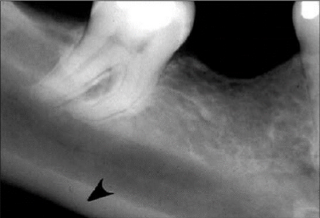

49. What is showing by arrow?

Mental Ridge (protuberance) On periapical radiographs of the mandibular central incisors, the mental ridge may occasionally be seen as two radiopaque lines sweeping bilaterally forward and upward toward the midline.